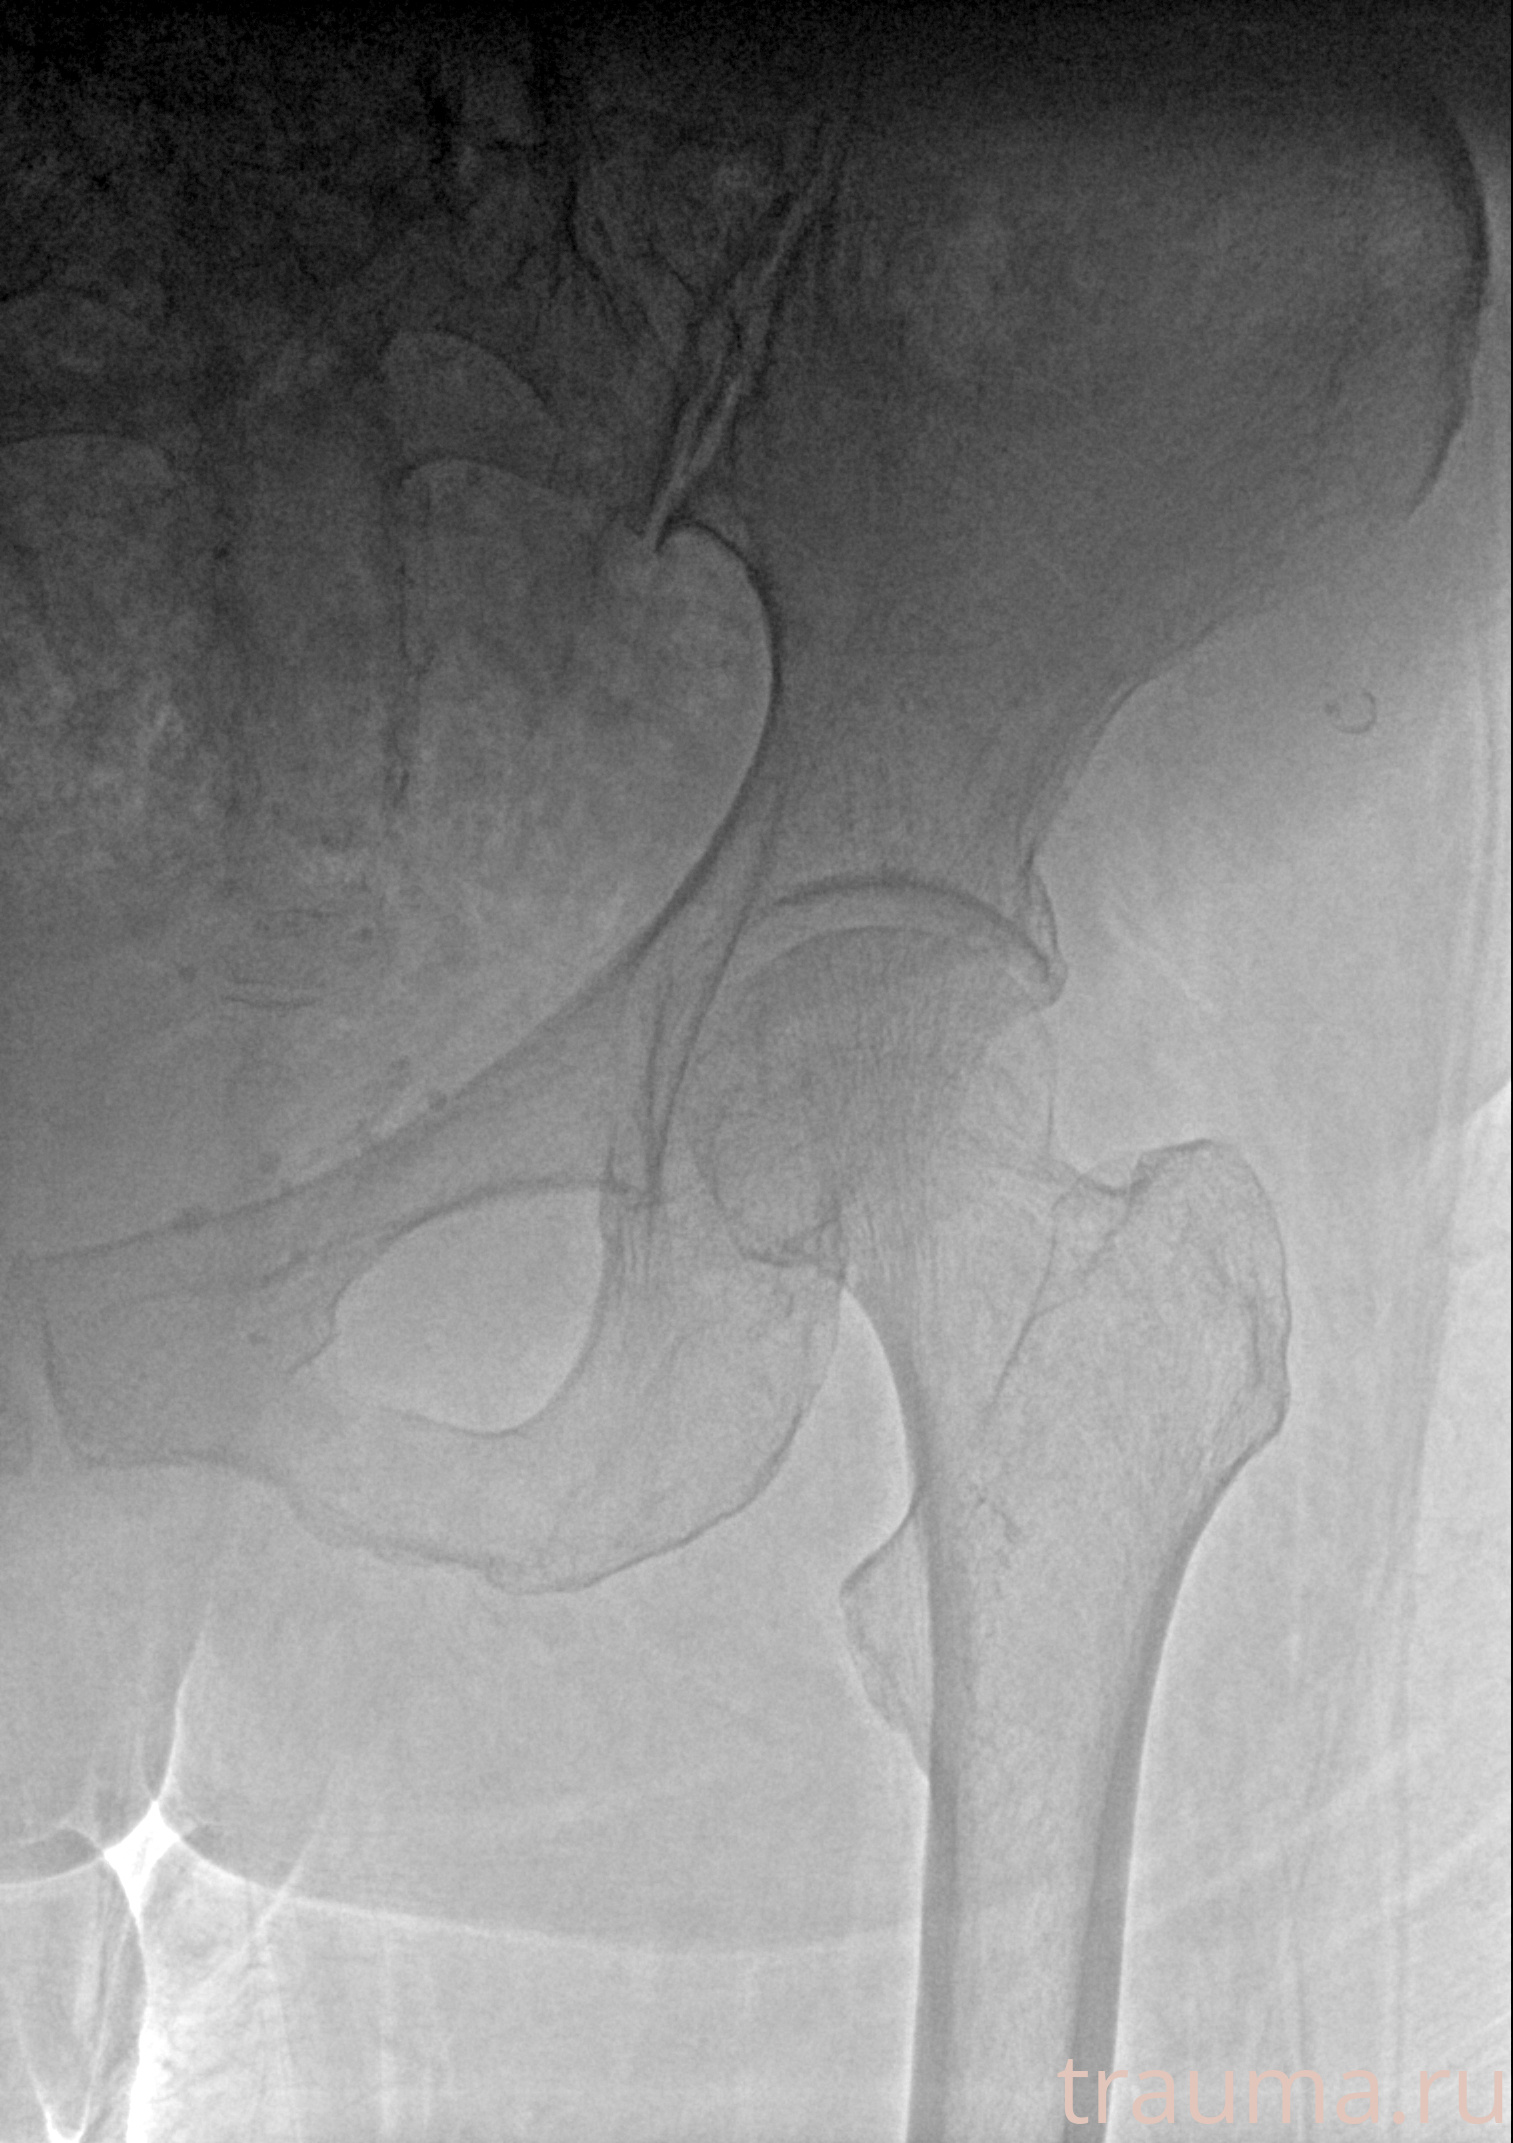

Первая помощь при переломе шейки бедра

Рентгенограммы

Рентген на дому: по вашему адресу приезжает врач-рентгенолог, травматолог-ортопед с мобильным рентгеновским аппаратом, проводит диагностику травмы или заболевания, делает необходимые рентгенограммы, дает рекомендации по дальнейшему лечению. Получить качественные снимки в домашних условиях возможно благодаря уникальной методике, разработанной МосРентген Центром для института  Склифосовского

при переломе шейки бедра и пневмонии от компании МосРентген Центр - партнера Института имени Склифосовского